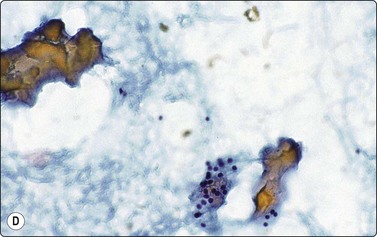

Fluid aspirated from cystic PC is uncharacteristic, brown or resembles altered blood. The diagnosis can easily be missed if well-preserved epithelial cells are scarce (Fig. 6.41).30,31,71 Presence of numerous macrophages, with many in cohesive clusters, should raise a suspicion of PC. Some of these cells are probably degenerating tumor cells exfoliated from the cyst lining (Fig. 6.42). They may represent foam cell metaplasia in tumor cells, and careful scrutiny will usually reveal nuclear features of PC. Large cell size, pseudoinclusions, nuclear grooves, and multiple well-defined vacuoles in atypical histiocytoid cells favor a diagnosis of PC.186

image

Fig. 6.41 Cystic papillary carcinoma

Cystic change in metastatic papillary carcinoma in cervical lymph node; mainly foamy cells with some pigment resembling macrophages; one cluster of degenerate atypical epithelial cells (MGG, HP).

image image

Fig. 6.42 Cystic papillary carcinoma

(A) Fluid from cystic papillary carcinoma; numerous macrophages, many with pigment, some clustered; a few nuclei with longitudinal grooves; no well-preserved epithelial cells (Pap, HP); (B) Tissue section from a cystic metastatic deposit in lymph node from same case; transition from intact neoplastic epithelium lining the cyst to exfoliated degenerating epithelial cells to ‘macrophages’ with intracytoplasmic pigment (HE, IP).

Tumor cells and tumor fragments in cyst fluid often show attenuation due to pressure of the cyst fluid and may not be recognizable as such in cytological and histological preparations. The sensitivity of FNA diagnosis in cystic neoplasms may be as low as 40%,31 and all cystic lesions should be managed cautiously. Combining clinical and cytological criteria and using US-guidance while needling minimize false-negative diagnoses.15 Cervical node metastases of PC are also often cystic and may not yield well-preserved diagnostic epithelial cells; the possibility of metastatic PC should be considered if samples of an abnormal cervical node contain only blood, fluid and histiocytes.

Smears from PC that show lymphocytes and multinucleated giant cells may simulate HT,42 especially the diffuse sclerosing variant of PC that shows heavy lymphocytic infiltration. Close scrutiny of nuclear features is essential to avoid false-negative diagnosis. Infiltration of follicular and Hurthle cells by lymphoid cells is suggestive of HT, papillary and three-dimensional clusters of cells indicate PC. HT and PC may coexist.109,187

Hurthle cell metaplasia of tumor cells may simulate HCT. If all of the tumor cells are of Hurthle cell type, an oxyphilic (Hurthle cell) variant of PC should be considered (described below).

Papillary foci (with rare psammoma bodies) are present in hyperplastic NG and in GD.188 Such hyperplastic lesions lack nuclear features of PC.